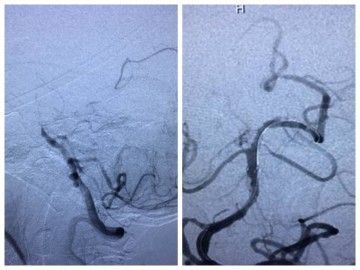

南医五院多学科合作开展首例“全脑动脉造影术、颅内动脉球囊扩张+支架植入术”

发布时间:2016-10-15 08:42:54

近日,南医五院神经内科联合介入诊疗科、麻醉科、重症医学部,顺利完成了从化区首例基底动脉重度狭窄病人“全脑动脉造影术、颅内动脉球囊扩张+支架植入术”。 一名68岁的阿姨突发头晕,感觉昏昏沉沉,曾到当地卫生院就诊,治疗数天后感到头晕加重,伴轻微头痛,恶心呕吐,饮水呛咳等,转至南医五院就诊,并收治老年科。神经内科会诊后...